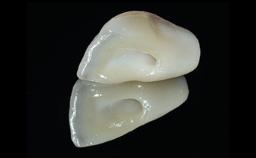

A 28-year-old patient presented at her general dentist’s office and complained about the appearance of her tooth 21. The patient had a history of trauma to this tooth. Endodontic treatment had been performed in the past and a crown placed on the tooth. A procedure to replace the old crown was performed by her dentist; however, a perforation on the middle third of the root occurred, and extraction of tooth 21 was suggested. Upon clinical and radiographic examination of the patient, who had been referred to us, replacement of tooth 21 by a dental implant appeared to be indicated.